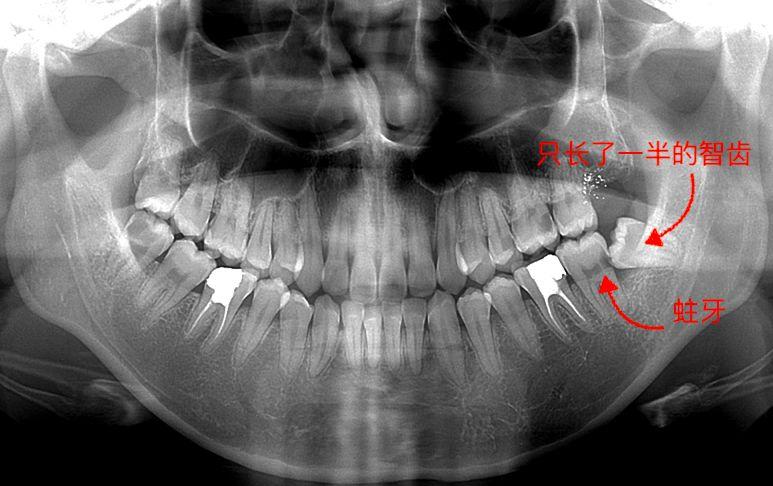

圖一,手指的這顆,很比別的牙矮,沒(méi)有長(zhǎng)出來(lái)是埋伏型的一顆,為什么去拔,因?yàn)樗鋵?shí)有頂我旁邊牙齒了,影響我這邊吃東西了,咬東西隱隱作痛,而且只要人不舒服這邊準(zhǔn)發(fā)炎和牙齦紅腫。

牙片,手指著的就是有問(wèn)題的智齒

長(zhǎng)歪的智齒不容易清潔,食物常常會(huì)留在智齒周?chē)?,不僅容易導(dǎo)致智齒疼痛,還容易導(dǎo)致智齒前方的磨牙變?yōu)橹溃瑥亩鸶蠓秶系难劳础?/p>

到了那個(gè)時(shí)候,智齒要拔掉不說(shuō),智齒前方的磨牙也會(huì)出現(xiàn)不可挽救的齲壞,只能一起拔掉。而且,智齒拔掉之后不需要鑲牙,多花個(gè)幾百一千塊。但如果前方的磨牙被拔掉,就只好通過(guò)種植牙進(jìn)行修復(fù),種一個(gè)牙齒,就得一萬(wàn)塊以上。

智齒前方的牙齒已經(jīng)出現(xiàn)蛀洞